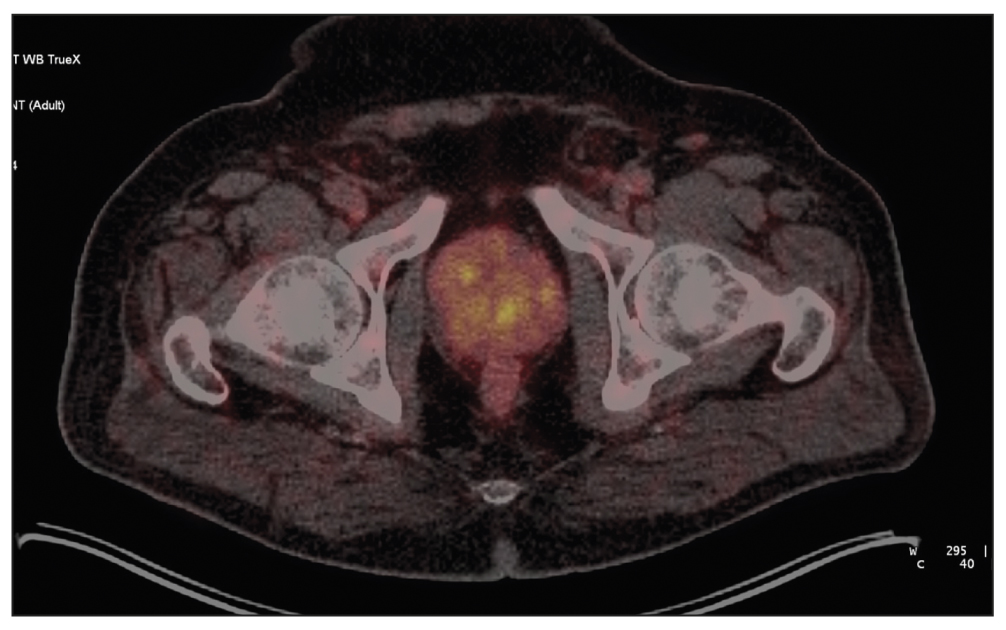

Patient M., 6 years old, had an increased PSA level of 6.8 ng/mL and underwent a multifocal prostate biopsy at a local clinic. The diagnosis was confirmed morphologically as adenocarcinoma, Gleason 6 (3 + 3), based on data from the transitory zone of the right prostate lobe. Adenocarcinoma elements were not found in other prostate biopsy specimens. Considering MRI evidence of changes in the same zone, implantation with 30 125I sources with a 32-cm3 volume was proposed.

SPECT/CT with 99mTc-HYNIC-PSMA revealed diffuse focal RP accumulation under the base of the bladder. PET/CT with 68Ga-PSMA-11 was additionally performed to more accurately visualize prostate lesions. PET/CT revealed multiple sites of RP accumulation in the prostate gland, indicating that the tumor was multifocal (Figure 8). Implantation planning was adjusted to include the total volume of the prostate gland (78 cm3) using 90 125I microsources (instead of preliminary 30 microsources).

Fig. 8. Patient M., 69 years old, PET/CT with 68Ga-PSMA-11: Sites of radiopharmaceutical accumulation in the prostate gland, multifocal tumor.

On February 25, 2022, implantation was performed for the total volume of the prostate gland. The initial prostate volume for brachytherapy was 32 cm3. PET/CT revealed a volume of 72 cm3 for implantation. The PSA level decreased to 0.31 ng/mL within a year after brachytherapy.